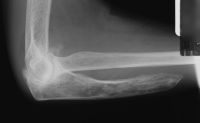

| Case 1. This 80 year old man developed wrist and elbow pain years after radial head excision for fracture. Radiographs show proximal migration of the radius resulting in valgus instability of the elbow, radiocapitellar impingement and distal ulnar impaction. This pattern of longitudinal forearm disruption, proximal radial fracture and dislocation of the distal radioulnar joint, is referred to as the Essex-Lopresti fracture dislocation. |